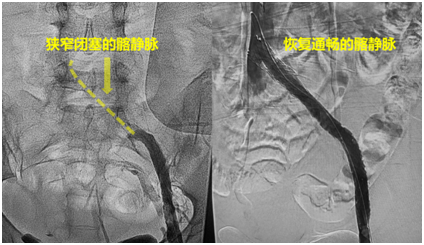

前因后果清楚了,那如何处理呢?很快,在厦心超声科的辅助下,庄晖对小胡进行了手术,先是找到了她小腿残留很短的一段健康静脉,然后通过超声引导精确穿刺,建立了手术的入路。在抽出大量血栓之后,小胡的腿部静脉终于恢复了通畅,而髂静脉狭窄也在造影下显露出来。在髂静脉狭窄的位置植入支架,扩开了静脉,让左腿的血液顺畅地回到了肺部和心脏。术后第二天,小胡就可以下地行走,两条腿都恢复了正常。

附图2:术前狭窄的髂静脉和术后通畅的髂静脉。